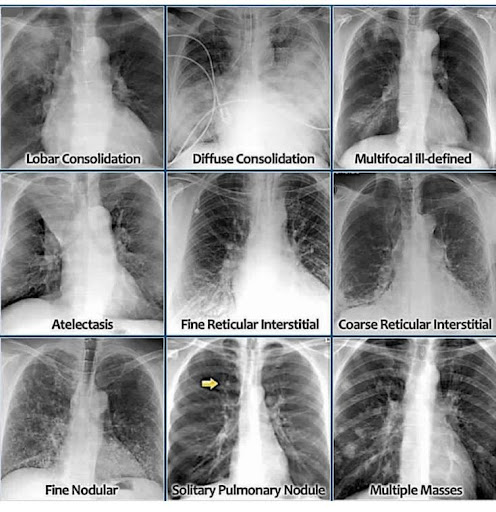

Pin by RHB1991 on medical info Radiology, Medical